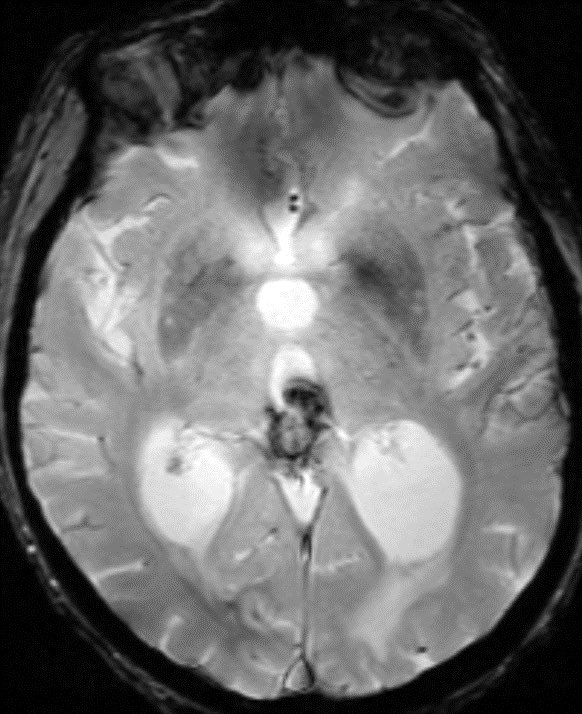

80 y/o patient presenting w/ headache is found to have a pineal mass and hydrocephalus. What is the most likely diagnosis and cause of the hydrocephalus?